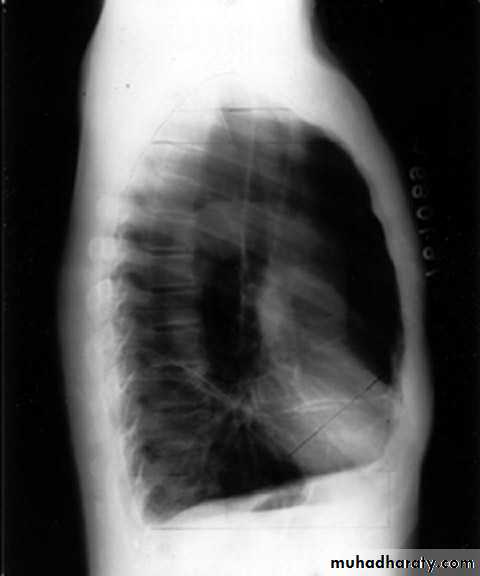

2- lateral.

rt lower lobe c. Left lower lobe c.